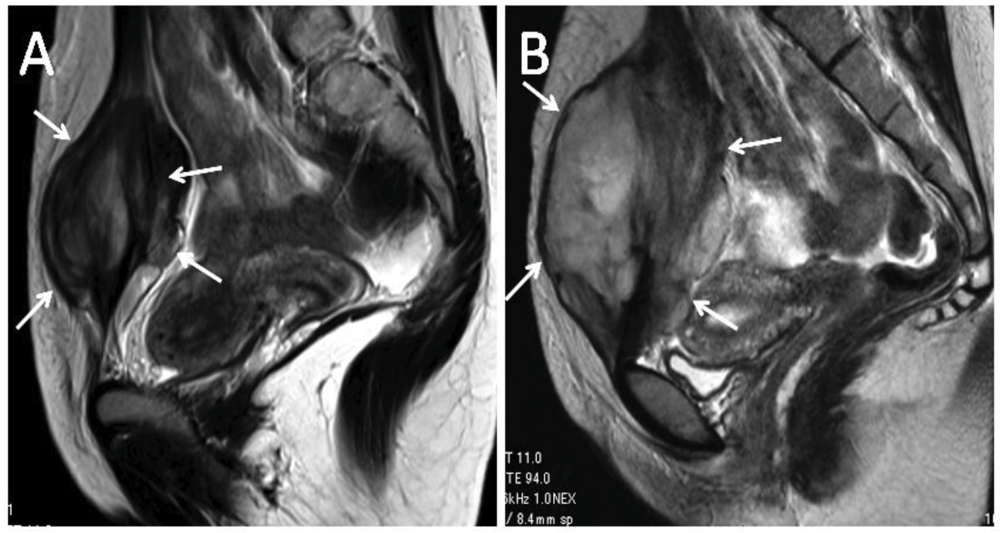

3. Conservative Therapy with Meloxicam (Since 2003)

- Nishida, Y.; Tsukushi, S.; Shido, Y.; Wasa, J.; Ishiguro, N.; Yamada, Y. Successful treatment with meloxicam, a cyclooxygenase-2 inhibitor, of patients with extra-abdominal desmoid tumors: A pilot study. J. Clin. Oncol. 2010, 28, e107–e109. [Google Scholar] [CrossRef]